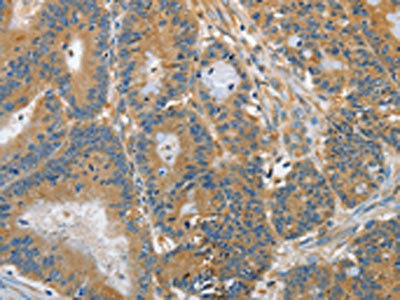

The image on the left is immunohistochemistry of paraffin-embedded Human cervical cancer tissue using CSB-PA049170(DGKZ Antibody) at dilution 1/60, on the right is treated with synthetic peptide. (Original magnification: ×200)

The image on the left is immunohistochemistry of paraffin-embedded Human colon cancer tissue using CSB-PA049170(DGKZ Antibody) at dilution 1/60, on the right is treated with synthetic peptide. (Original magnification: ×200)